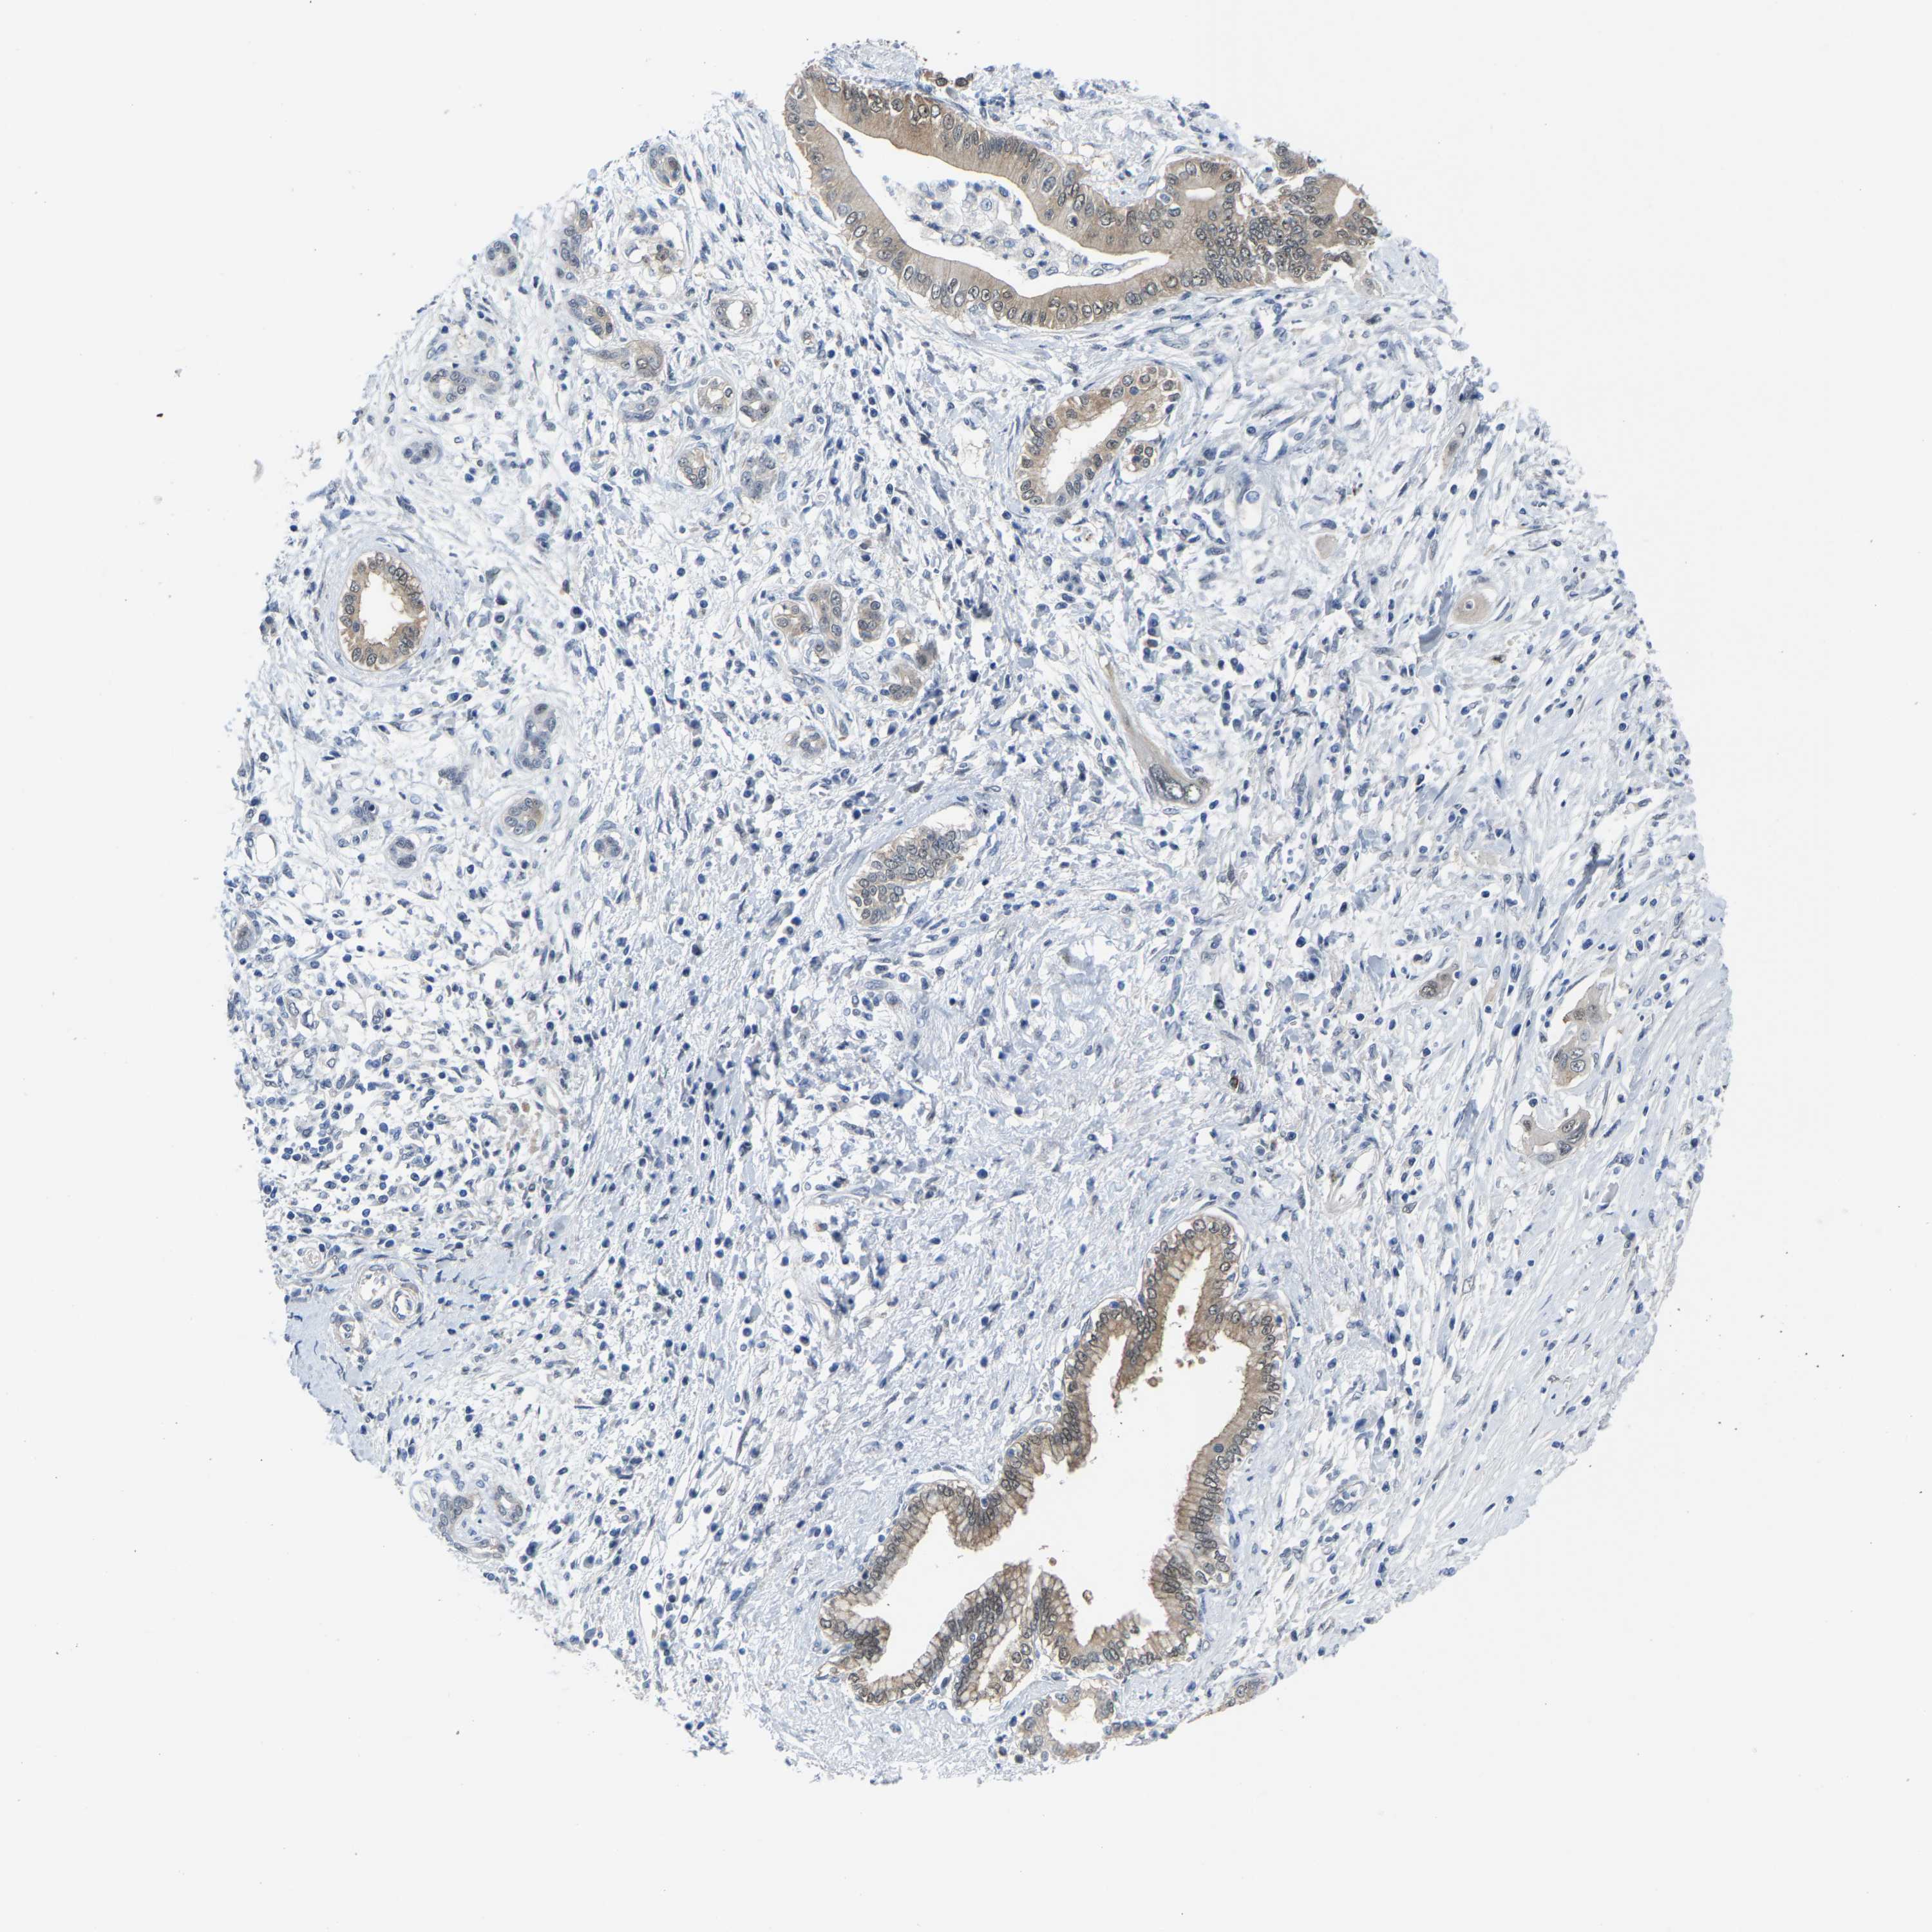

PANCREATIC CANCER - Protein expressioni

A mouse-over function shows sample information and annotation data. Click on an image to view it in a full screen mode. Samples can be filtered based on level of antibody staining by selecting one or several of the following categories: high, medium, low and not detected. The assay and annotation is described here.

Note that samples used for immunohistochemistry by the Human Protein Atlas do not correspond to samples in the TCGA dataset.

Antibody stainingi

Antibody staining in the annotated cell types in the current human tissue is reported as not detected, low, medium, or high, based on conventional immunohistochemistry profiling in selected tissues. This score is based on the combination of the staining intensity and fraction of stained cells.

Each image is clickable and will lead to virtual microscopy that enables deeper exploration of all samples and also displays staining intensity scores, fraction scores and subcellular localization as well as patient and tissue information for each sample.

Antibody HPA019949

Antibody HPA019957

Staining

High

Medium

Low

Not detected

Intensity

Strong

Moderate

Weak

Negative

Quantity

>75%

75%-25%

<25%

None

Location

Nuclear

Cytoplasmic/membranous

Cytoplasmic/membranous,nuclear

Adenocarcinoma, NOS